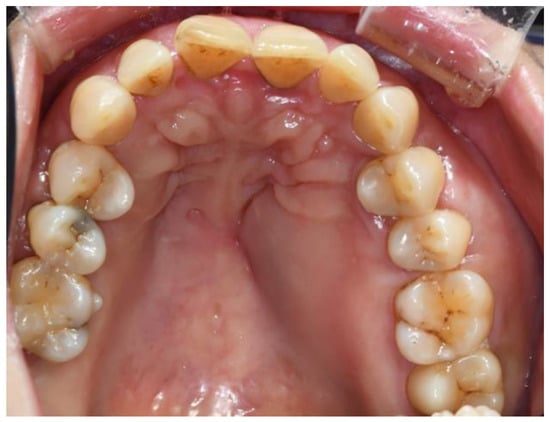

2.1. Clinical Presentation

2.2. Differential Diagnosis

2.3. Diagnosis and Management